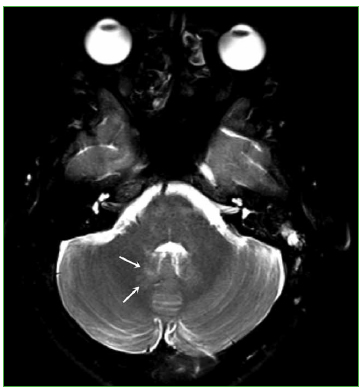

La RM de cerebro reveló anomalías menores en la fosa posterior (Figura 9), sin alteraciones evidentes en el compartimento supratentorial (lo que coincide con los escasos síntomas neurológicos de esta paciente). La RM de columna fue normal.

Figura 9. Resonancia magnética, corte axial potenciado en T2 con supresión grasa

(5470/95) de cerebro. Se reconoce una  sutil alteración de señal en la topografía del

núcleo dentado derecho (flechas).